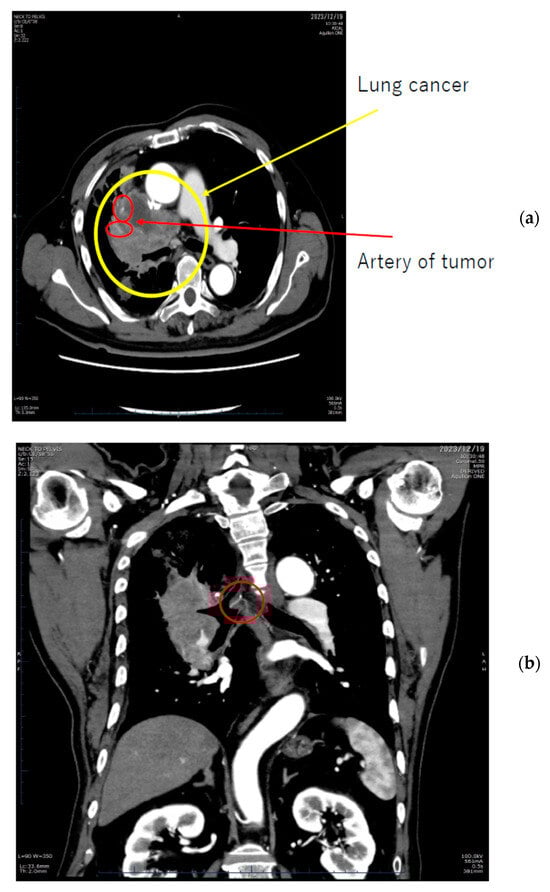

- AI for Image Analysis: AI-based image analysis algorithms can enhance the detection and diagnosis of extravasation events in imaging studies, such as ultrasound, MRI, and CT. These algorithms can automatically identify subtle signs of extravasation, assist healthcare providers in interpreting the imaging findings, and facilitate a timely intervention. This suggestion is subsequently extended as a separate discussion.